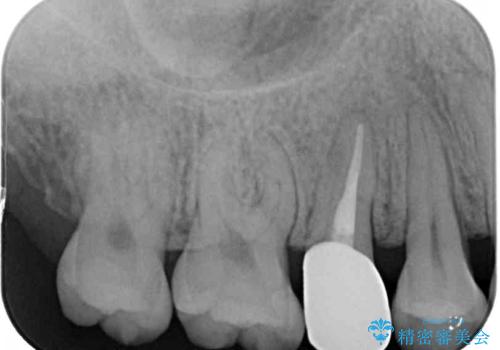

神経が死んで変色した歯 根管治療とオールセラミッククラウン

- 近医にて右上奥歯に大きなむし歯があると指摘されたとのことで来院された患者様です。

診査の結果、既に歯の神経は失活して変色しておりましたが、特に痛みは認めませんでした。

根管治療を行った後にオールセラミッククラウンにて補綴することとしました。

補綴後6ヶ月経過しレントゲンを撮影したところ、根尖周辺の病変が消失していることが確認できました。